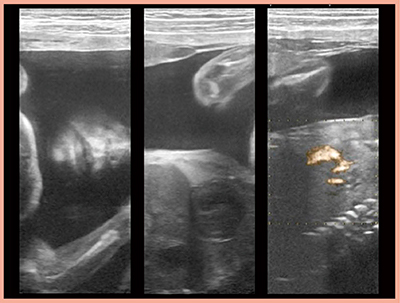

4G CMUTは,超広帯域化したことで,プローブを持ち替えることなくさまざまな領域の検査が可能であり,非常に便利である。実際に,乳腺の設定のまま胎児を撮像したところ,顔のしわや唇の動き,心臓の動き,臍帯血流などが明瞭に描出された(図7)。先天的な胎児異常の診断や胎児手術のガイドにも有用と考えられた。さらに,4G CMUTの高い透過性により,骨の後方や,双子の羊膜の境界,頭蓋内の構造まで視認可能であり,高い将来性を感じている。

図7 4G CMUTによる胎児の描出